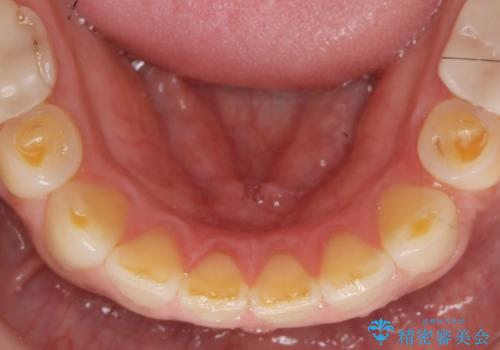

歯ぎしりですり減った 前歯の見た目を回復したい

- 歯ぎしり・嘔吐症により歯がすり減ってしまい、色調・見た目を改善したいと来院されました。

神経を温存したまま仮歯に置き換え、噛み合わせの安定を確認したのちに すり減りに強いジルコニアクラウンで最終的な仕上げを行います。

- 145.2万円(仮歯・ジルコニアクラウン×12歯)費用は治療当時の料金となります